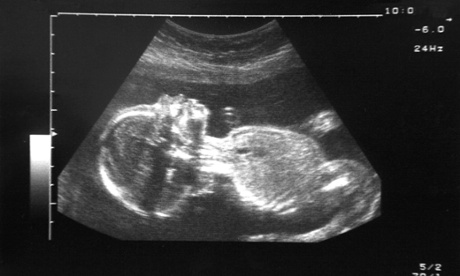

ultrasound fetus

Some choices aren’t easy. Photograph: Craig Holmes Premium/Alamy